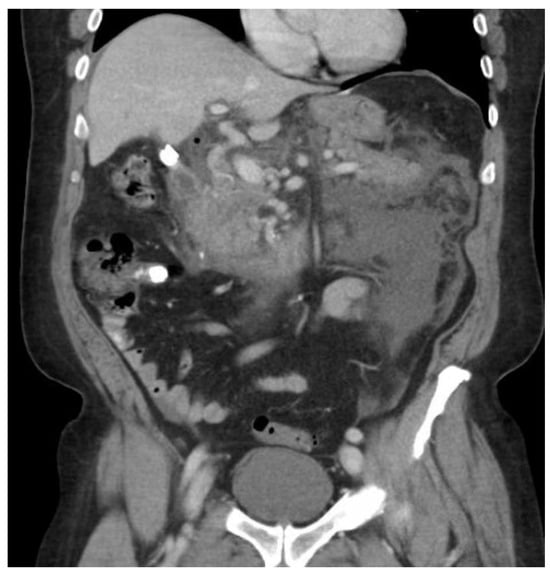

Multiple cytokines mediate a powerful pro-inflammatory immune response, such as tumor necrosis factor-alpha (TNF-a) and interleukins 1a, 1b, 6, and 18, exacerbating the initial pancreatic injury [37]. Pathologically, this appears as inflammation and can also be associated with a hemorrhage at the microscopic level (Figure 2 and Figure 3). The cytokine-mediated inflammatory cascade then extends the inflammatory cascade via lymphatic and systemic circulation into the liver, lungs, heart, kidneys, and gastrointestinal (GI) tract, leading to multi-organ injury [38]. This can cause systemic inflammatory response syndrome (SIRS), an early clinical feature that persists in cases of severe acute pancreatitis. Inflammation and damage to the GI tract can lead to bacterial translocation [39], and the species of bacteria involved are a predictive factor of disease severity, with Enterococcidae most frequently being associated with severe disease [40]. Obesity is also a predictive factor for moderate severity, and it leads to further deleterious effects through adipocyte lipolysis in the pancreas and adipose tissue [41,42] (Figure 2 and Figure 3).

3.2. Severity of Pancreatitis

Figure 1. Severe necrotizing pancreatitis.